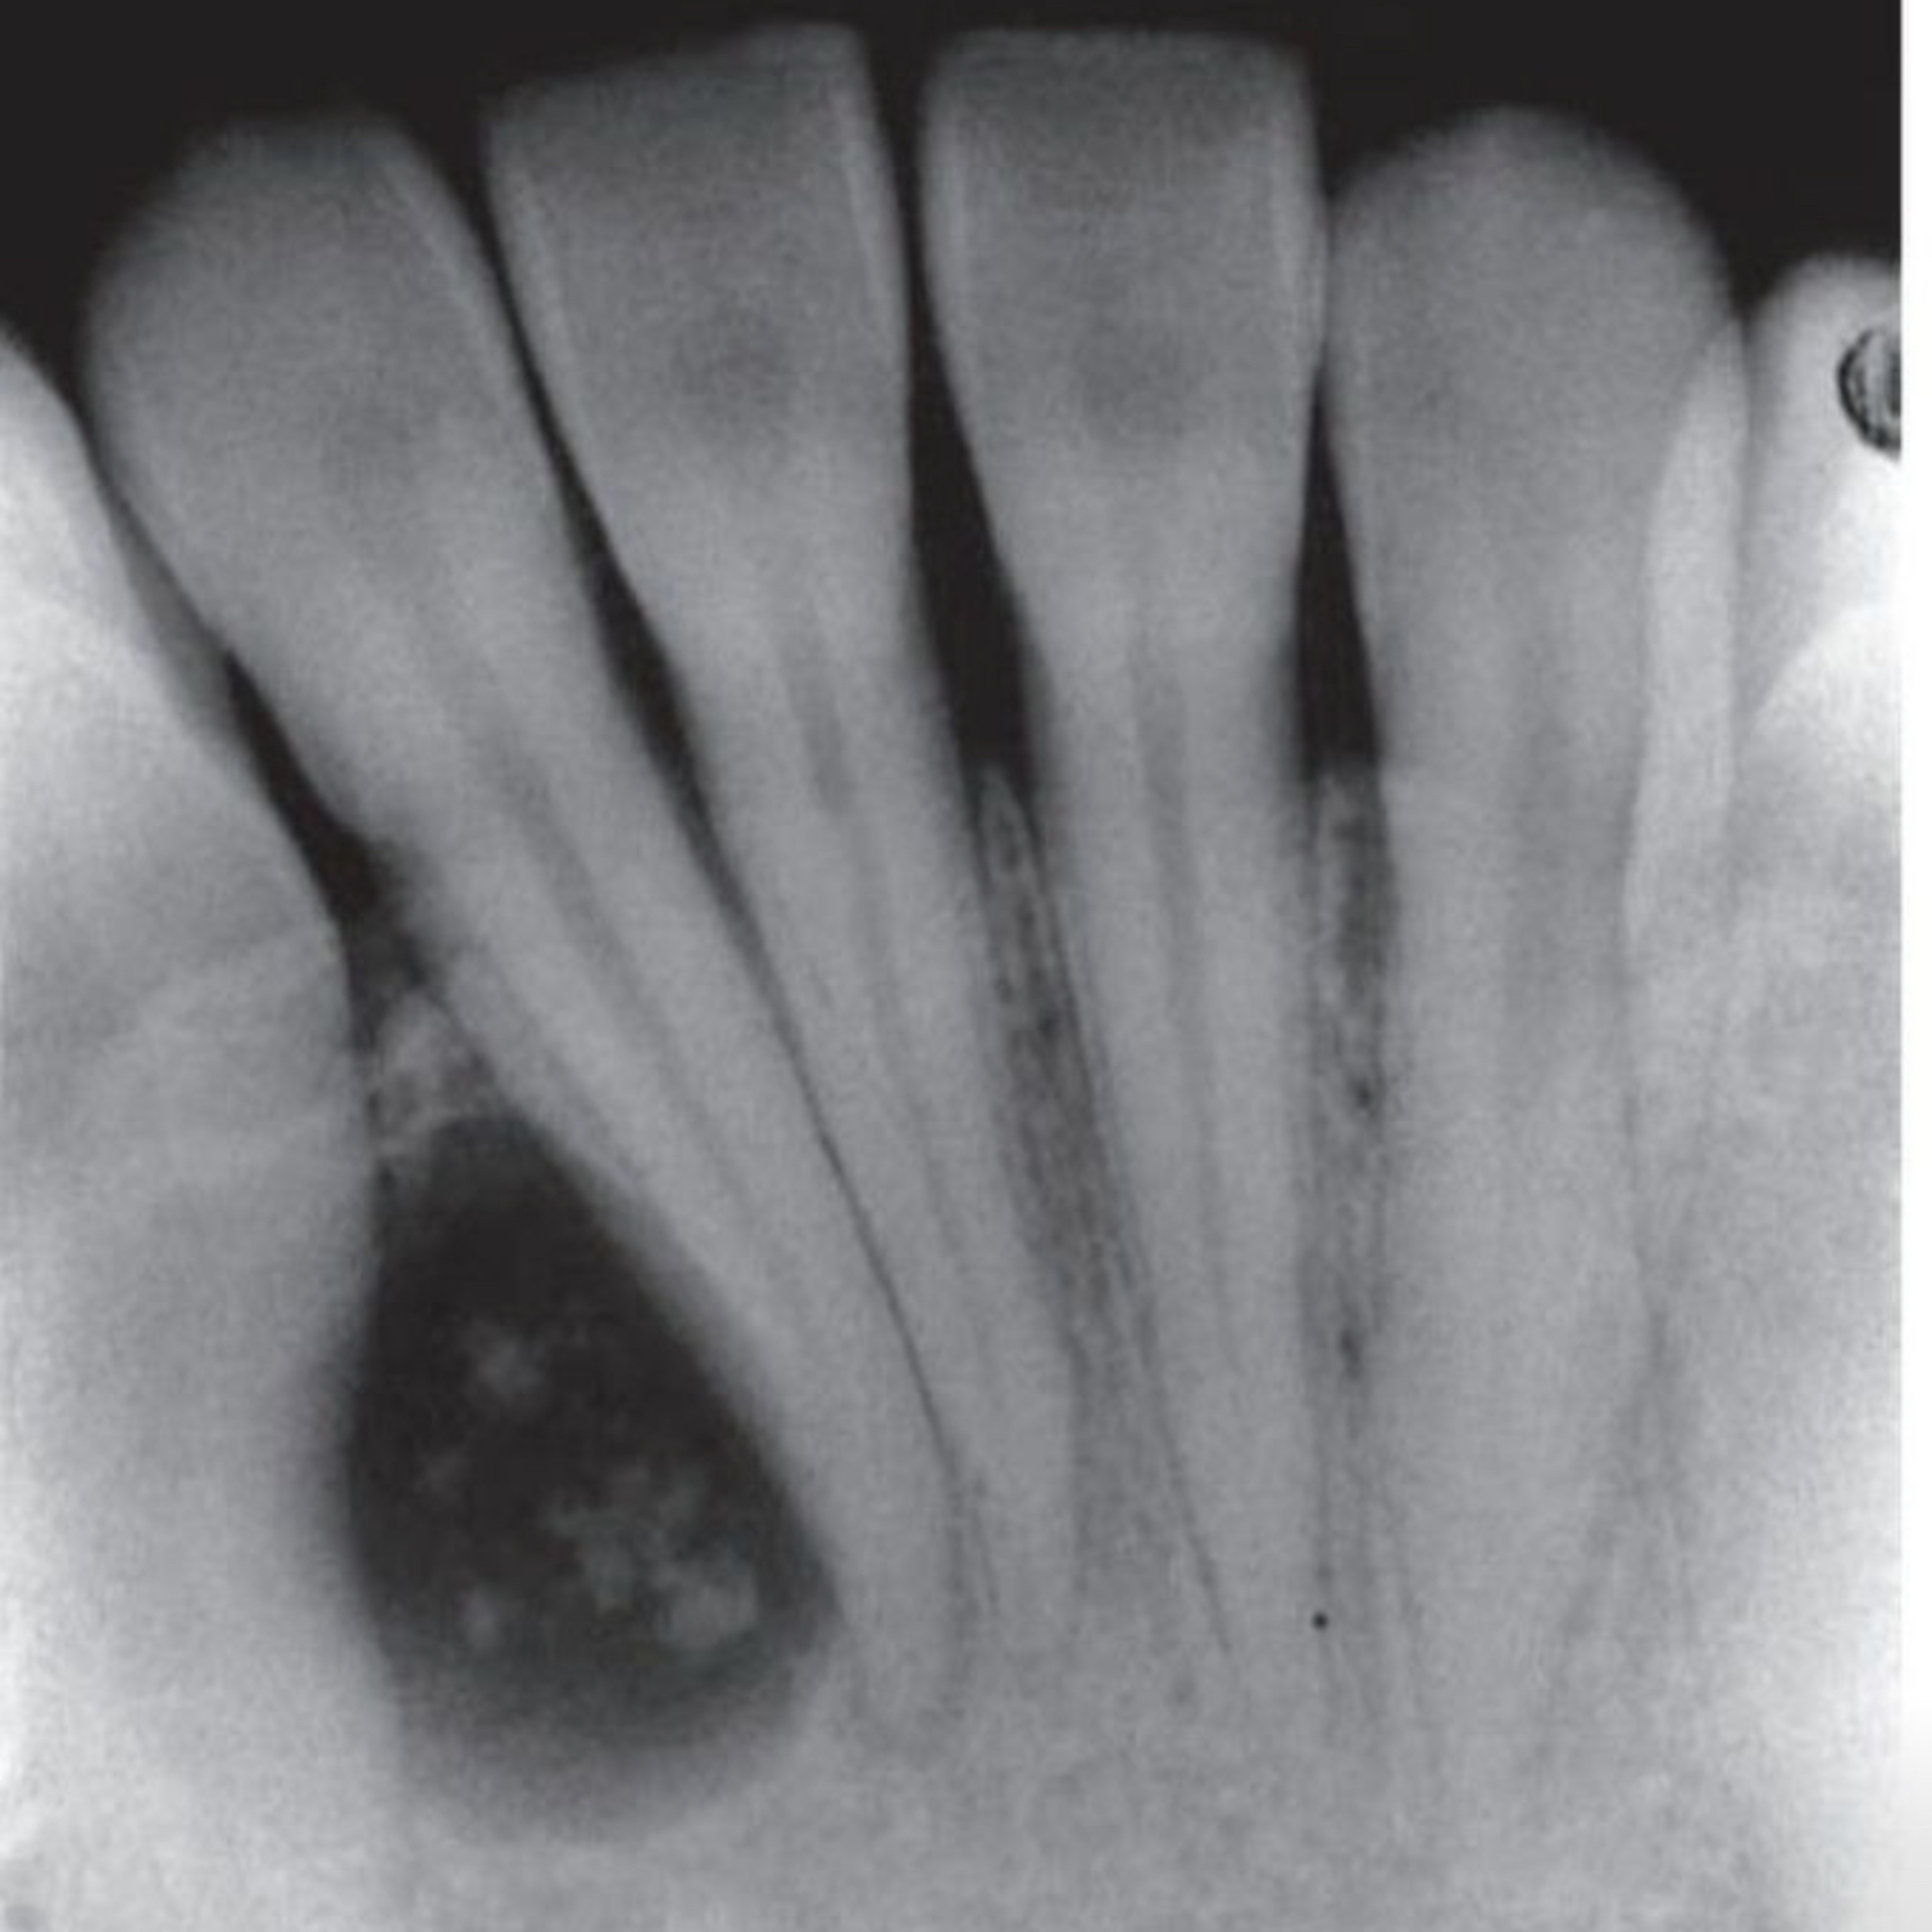

The adenomatoid odontogenic tumor (AOT) is a benign epithelial odontogenic tumor, slow-growing and well-demarcated. The AOT is classified into three variants: follicular, extrafollicular, and peripheral.

• Radiographically, it appears as a well-defined radiolucency around the crown, extending along the root.

• Mimics a dentigerous cyst but shows tumor-like behavior.

• Definition: Occurs independently of unerupted teeth, commonly in the anterior maxilla.

• Appears as a solitary radiolucency with varying degrees of radiopacity from calcifications.

1. Saleh, Z. (n.d.). Periapical radiograph of anterior mandibular incisors showing radiolucency. Retrieved from https://lnkd.in/dPR3SstP